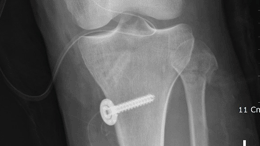

무릎십자인대수술

• 그림